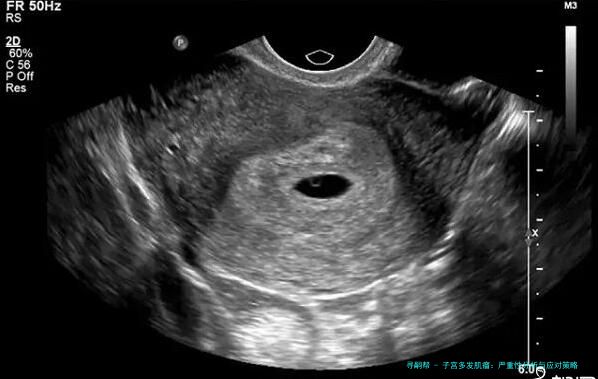

首先,子宫多发肌瘤简单来说,就是子宫里长了不止一个肌瘤。这些肌瘤是良性的肿瘤,由平滑肌和结缔组织组成,通常不会癌变。症状因人而异,有的人可能完全没感觉,而有的人则会经历月经量增多、腹痛、腰酸背痛,甚至影响排尿或生育。举个例子,我认识的一位阿姨,她就是因为月经期太长、量太大,才去医院检查,结果发现是多发肌瘤。医生说,这病在中年女性中更常见,但近年来年轻女性发病率也有上升趋势,可能跟生活压力大、饮食不规律有关。

说到严重性,这得看情况。从数据上看,大多数子宫多发肌瘤并不致命,属于可控的良性病变。根据近年医学研究,大约70%-80%的患者可以通过保守治疗或定期观察来管理,只有少数情况需要手术干预。比如,如果肌瘤大小超过5厘米,或者导致严重贫血、不孕等问题,那可能就比较棘手了。但别慌,我查了查资料,发现近年来微创手术技术进步很快,很多患者术后恢复得不错,生活质量也没受太大影响。不过,如果拖延不治,可能会加重症状,甚至引发并发症,比如贫血导致乏力、头晕,或者压迫膀胱引起尿频。所以,它不算绝症,但也不能掉以轻心。

治疗方面,选择挺多的。轻度的可以通过药物控制,比如用激素类药物调节月经;中重度的可能需要手术,比如子宫肌瘤剔除术或子宫切除术。近年来,微创技术如腹腔镜手术越来越普及,恢复快、创伤小。预防上,建议定期体检,尤其是B超检查,能早发现早处理。饮食上,多吃蔬菜水果,少吃红肉和高脂食物;运动也不能少,每周坚持散步或瑜伽,能帮助调节激素水平。我个人觉得,心态也很关键——别一听说肌瘤就恐慌,多和医生沟通,制定个性化方案,才是上策。